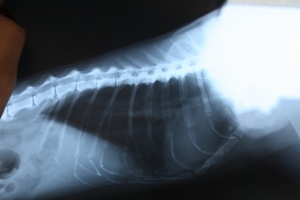

Рентген сегодня показал полное поражение легких - развились метастазы.

Рентген, который мы у тебя нашли, кажется еще я делала - там нет метастаз.

А вот в сравнении: